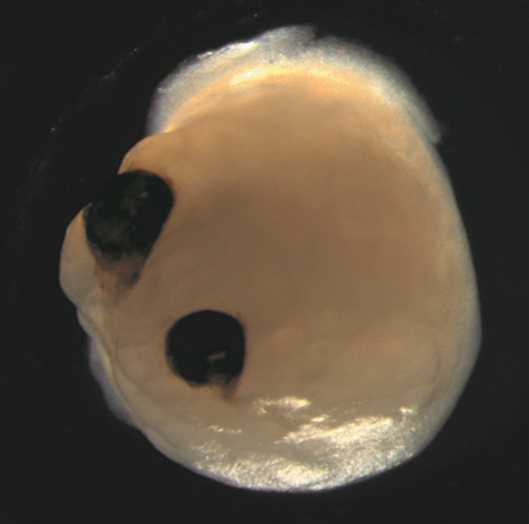

包含视杯的大脑类器官。图片来源:德国杜塞尔多夫大学医院/Elke Gabriel

8月17日,发表在《细胞—干细胞》上的一项研究显示,人类诱导多能干细胞(iPSCs)可以用来生成包含视杯的大脑类器官。视杯是眼睛中的一种结构。该类器官能自发地从类脑区前部发育出双侧对称视杯,显示出iPSCs在高度复杂的生物学过程中固有的自我模式形成能力。

为了实现这一目标,Gopalakrishnan和团队修改了他们之前开发的将iPSCs转化为神经组织的方案。最终,他们生成的大脑类器官形成了视杯。该结构最早在30天内出现,50天内成熟为可见结构。这个时间框架与人类胚胎视网膜发育时间框架相吻合,因此可以使某些类型的发育神经生物学实验更有效。

利用来自4名捐赠者的16个独立批次iPSCs,研究人员生成了314个大脑类器官,其中72%形成了视杯,这表明该方法是可重复的。这些结构包含不同类型的视网膜细胞,它们形成了能对光线作出反应的电活性神经元网络。含有视杯的大脑类器官也包含晶状体和角膜组织,并且视网膜与大脑相应区域相连。